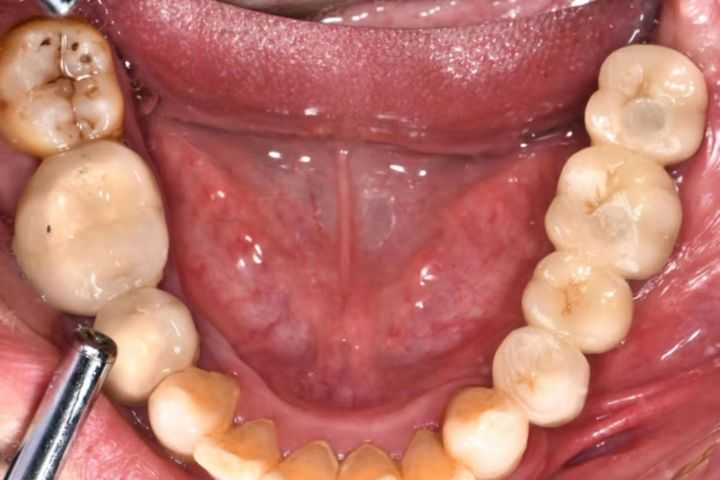

下面是一組利用種植導(dǎo)板做的種植案例:

下面這組案例,種植牙修復(fù)冠破損,拆卸后,頸部有一片粘接劑。

激光筆照射后,發(fā)出粉色熒光,這說(shuō)明有細(xì)菌感染。粘接劑殘留,是一個(gè)嚴(yán)重的菌斑滯留因素。一般的種植醫(yī)生不懂修復(fù),可能會(huì)出現(xiàn)這種問(wèn)題。